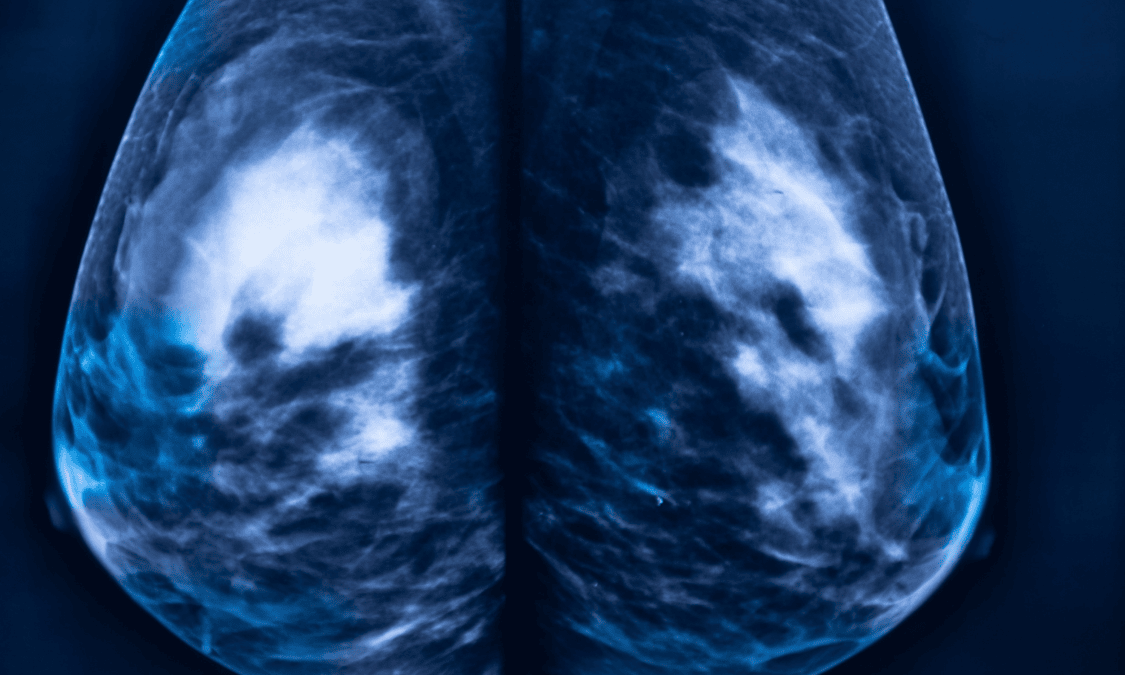

Comprehensive Breast Imaging & Diagnostics

Mammogram services in Nairobi

We combine screening and diagnostic imaging in one platform, including 3D mammography for superior accuracy. This helps detect cancers earlier, even in dense breast tissue, when treatment is most effective.

Our Siemens Mammomat 3000 system delivers sharp, detailed images with reduced false positives. That means fewer call-backs, less anxiety, and faster clarity when you need it most.